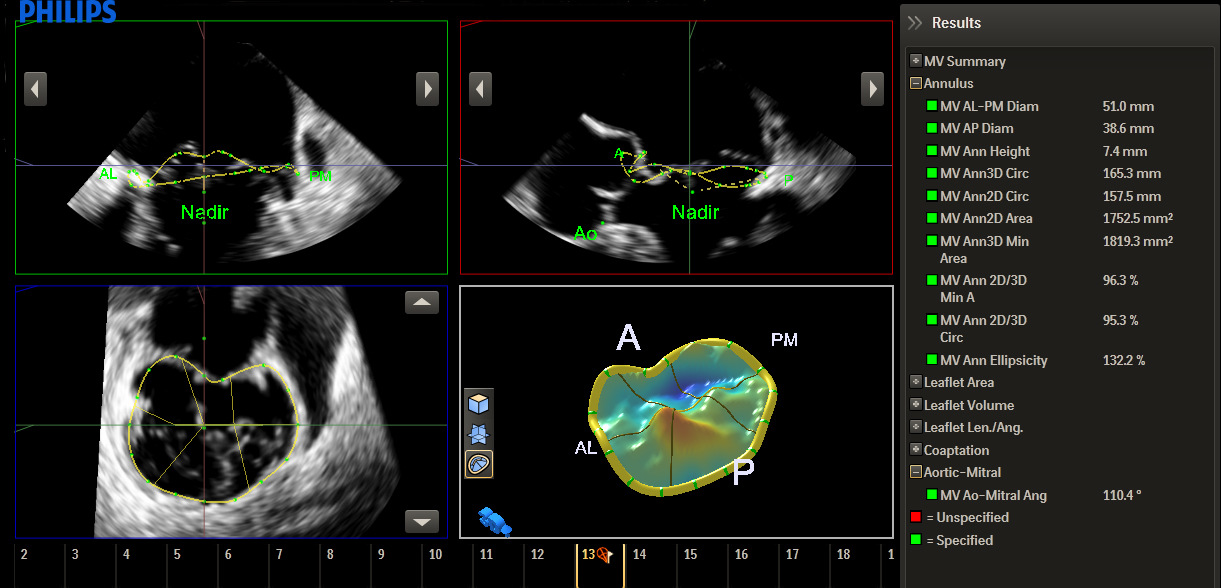

HeartModelᴬ⋅ᴵ⋅— это новое приложение для УЗИ с технологией интеллектуального анализа анатомии (AIUS), предлагающее передовые средства количественной оценки трехмерных данных в реальном времени, автоматизированное создание двумерных проекций и уверенное получение воспроизводимых результатов в эхокардиографии. Приложение HeartModelᴬ⋅ᴵ⋅ автоматически определяет, сегментирует и количественно оценивает левое предсердие (ЛП) и левый желудочек (ЛЖ) в трехмерных объемных данных.

Согласно результатам сравнительного исследования двумерного количественного анализа и анализа в режиме Live 3D HeartModelᴬ⋅ᴵ⋅ приложение HeartModelᴬ⋅ᴵ⋅ позволило сэкономить 82% времени при работе в полностью автоматическом режиме и 71% времени при минимальном ручном редактировании.

Благодаря повышенной воспроизводимости и выполнению меньшего количества этапов за меньший промежуток времени, чем требуется для традиционных методов, больше пользователей смогут увереннее проводить диагностику.